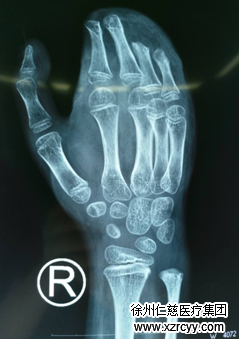

6岁男童右手卷进压面机,伤势严重

于是他们在旁人的建议下赶快去betway在线登陆,接受更专业、更权威的治疗。当孩子和家属赶到时,必威官方首页官网betway接诊医生坦率地告诉患者家属:孩子病情不容乐观,伤口挫伤较重,右手脱套,血管神经肌腱损伤,挫伤重,手掌、手背皮肤毁损不成型,术中有移植血管的可能。如此重的伤情,首先要保住孩子的右手,后面需要多次手术修补创面,后期康复功能锻炼,才能恢复患肢功能。小虎家人心痛地说:“孩子还小,伤的是右手,以后该怎么办,请你们千万救救我的孩子!”医生表示一定会尽最大努力,不能让孩子这么小就残废了。

小虎被推入手术室,黎章灿手术团队协力合作,由于伤口挫伤污染较重,一期清除创面污染、失活组织,修复断裂的血管、神经、肌腱,首先确保患肢成活,经过2小时手术,小虎被推出手术室,术后给予抗感染对症治疗。中间经过两次清创,小虎右手创面清洁,满足皮瓣修复条件。手足显微外科的专家们组成讨论组,对如何修复右手创面展开激烈讨论,最终确定手术方案,取“右股前外皮瓣+髂腹股沟皮瓣修复右手皮瓣”。随后,医生告知患者家人患者病情及下一步治疗方案,患者家人表示理解,并确定下手术日期,在黎章灿手术团队通力合作下,经过3小时努力,顺利将小虎右手创面覆盖,后期小虎好转出院,告知小虎家人锻炼方法及后期治疗方案。